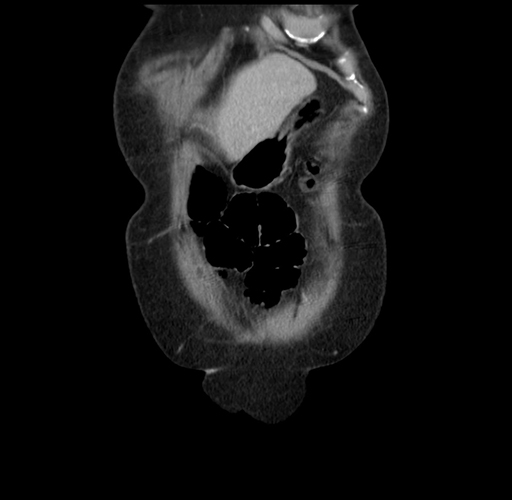

Pre-Chemo: Axial Venous

Axial Venous